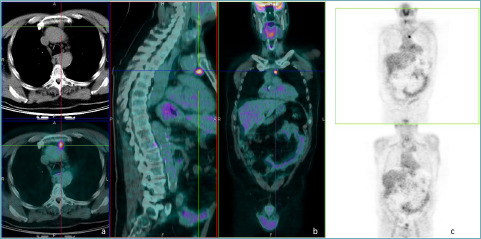

Cholesterol granuloma. Another brick in the wall of mediastinal lesions.